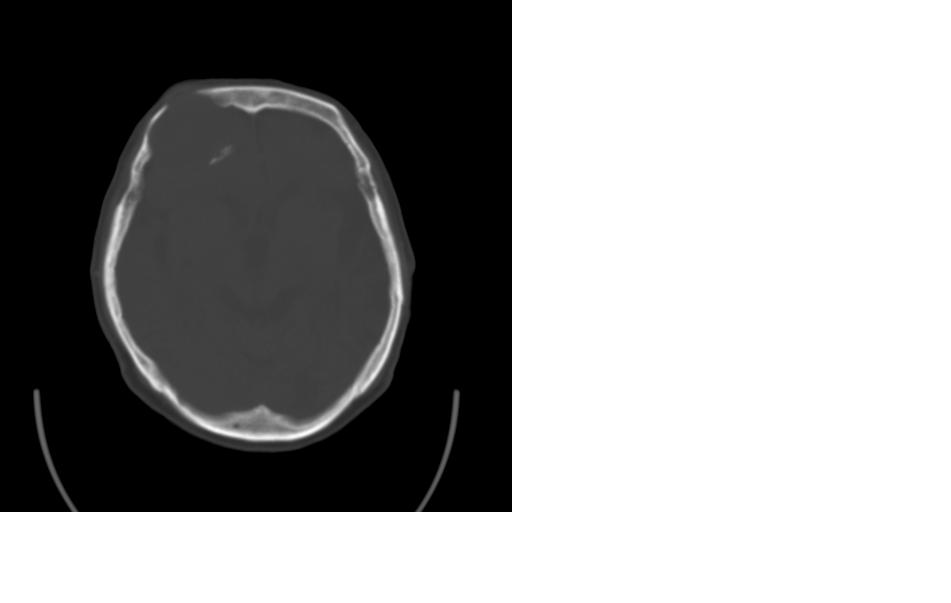

女,77岁,渐进性突眼2年,无其他明显症状

右侧额部软组织密度肿块,界限不清,明显向前下方增长,占位效应明显,内见钙化,局部颅骨明显吸收.考虑:右额叶脑膜瘤.建议:增强

额骨右侧呈明显膨胀性骨质破坏,内外板明显变薄.考虑骨巨细胞瘤或动脉瘤样骨囊肿的可能性大。

定位:来源右额窦。定性:良性占位—额窦黏液囊肿。理由1、病灶中心位于右额窦区,侵及筛窦并向下向前压迫眼球2、骨质呈膨胀性改变,骨质弓形变薄但骨壳完整,如为恶性骨质应为侵蚀性破坏3、黏液囊肿好发于筛窦、额窦。